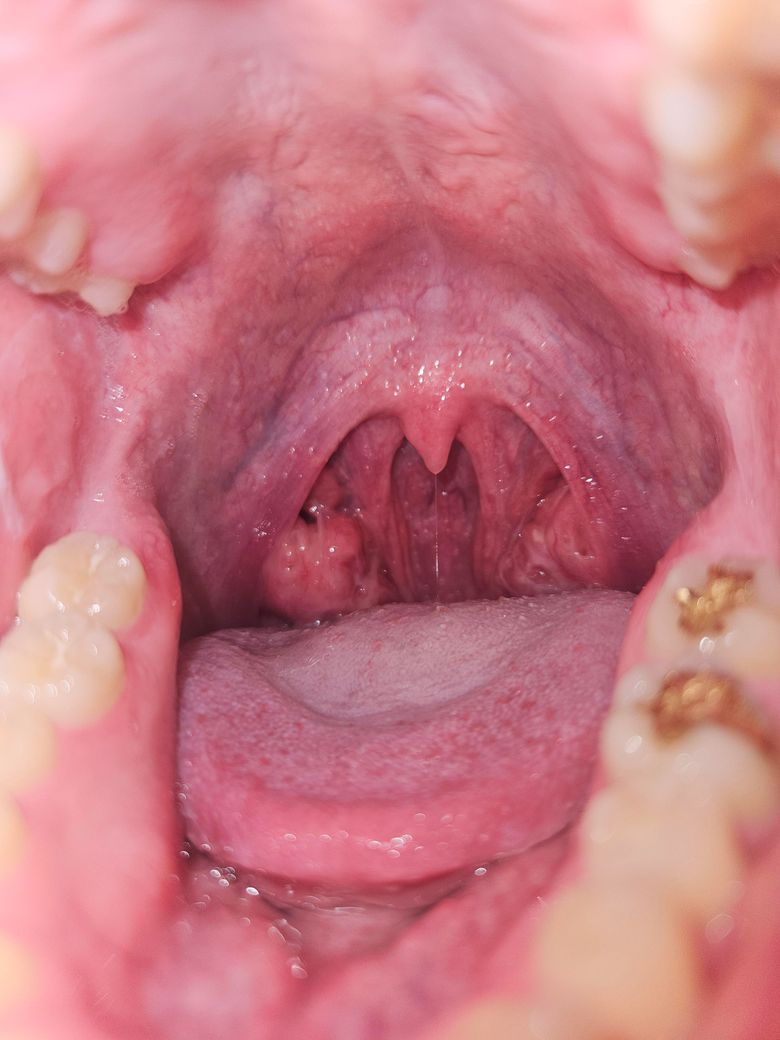

사진에서 보이듯이 오른쪽 편도에 볼록한게 보여서요, 혹시 종양일까요?

어렸을 때부터 편도가 크다고 병원에서 듣긴 했습니다.

실제로 사진에 올려주신 것과 같은 비대칭적인 편도의 크기 변화는 양성 변화인 경우가 더 많습니다.

편도에는 음식물 찌꺼기, 죽은 세포 등이 쌓여 딱딱한 편도 결석이 생기기도 합니다. 이 결석은 노란색 또는 흰색의 돌처럼 보이며 냄새가 날 수 있습니다. 크기가 크면 혹처럼 보일 수도 있습니다.

편도 낭종도 드물지만 발생할 수 있으며 대부분 양성입니다. 특별한 증상이 없으면 큰 문제는 아닙니다.

어릴 때부터 편도가 크다는 설명을 들었다면 선천적으로 편도가 비대칭적으로 큰 것일 수도 있겠습니다.